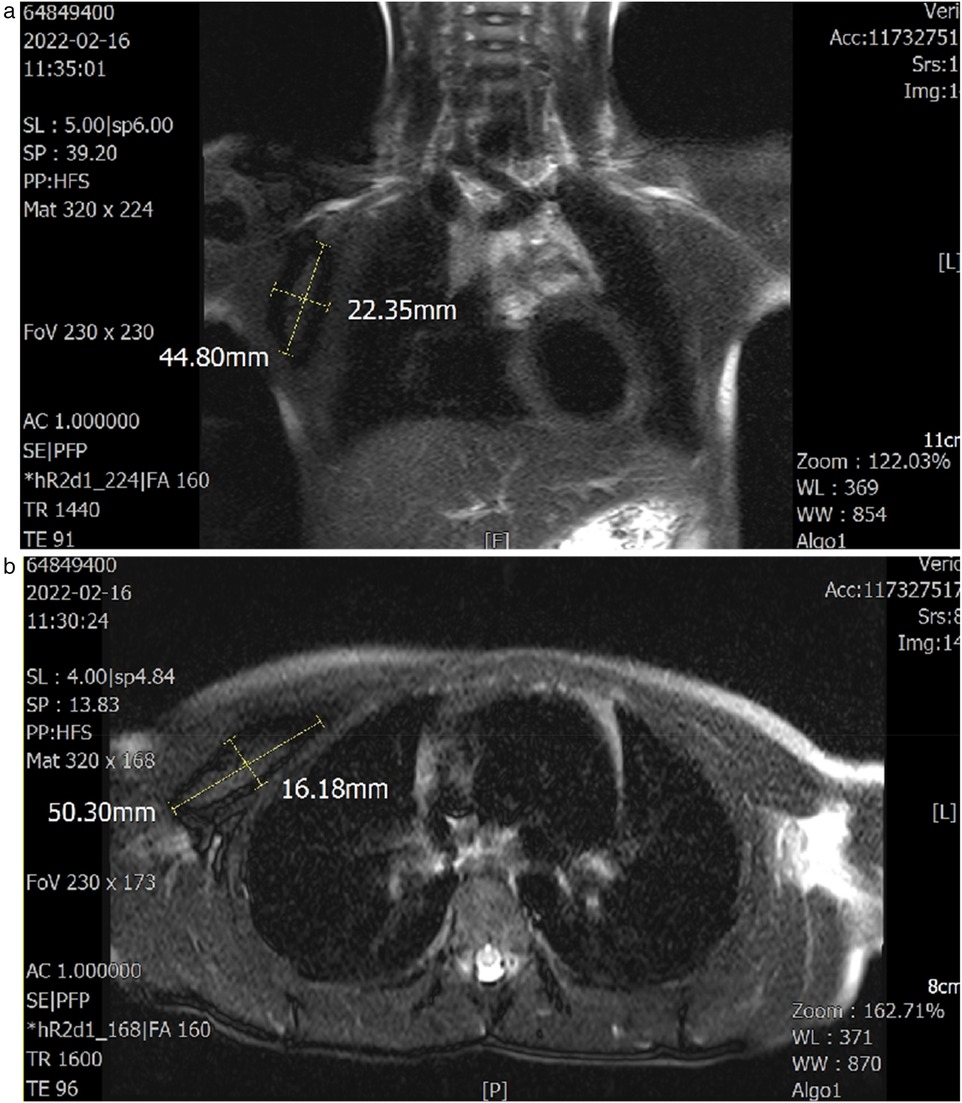

A 6-year-old girl patient was admitted to our hospital with a 5-year history of progressive enlargement of a right chest subcutaneous mass. General physical examination and blood biochemical tests were normal, with unremarkable personal history. Chest MRI demonstrated a lobulated slightly short T1 signal mass in the intermuscular space between the right pectoralis major and minor muscles. The lesion exhibited peripheral low signal on fat-suppressed T2-weighted imaging (fs-T2WI) with patchy central hyperintensity, measuring approximately 2.3 × 5.0 × 5.5 cm in maximum cross-section. Diffusion-weighted imaging (DWI) revealed isointense to slightly hyperintense signal characteristics (Figure 1). These imaging features supported the diagnosis of IA in the pectoral muscle space.

Composite medical imaging displaying two MRI scans. The top image is a coronal view of the neck area, measuring dimensions of 44.80 millimeters and 22.35 millimeters. The lower image shows an axial view of the thoracic cavity, with measurements of 50.30 millimeters and 16.18 millimeters. Both images include detailed annotations and measurement markers.

Figure 1. (a,b) Axial and coronal T1- and T2-weighted images demonstrate the lesion site and dimensions. The sagittal plane was unremarkable.